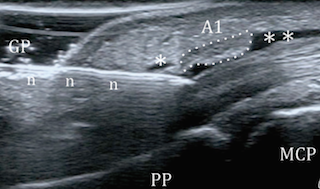

Ο εκτινασσόμενος δάκτυλος (trigger finger) είναι μια συχνή πάθηση σε ανθρώπους που κάνουν επαναλαμβανόμενη κάμψη (λύγισμα) των δακτύλων. Οι τένοντες που κάνουν αυτή την κίνηση σε κάθε δάκτυλο πορεύονται κάτω από συνδέσμους που τους κρατούν στη θέση τους. Σε έναν από αυτούς τους συνδέσμους (που λέγεται Α1 και βρίσκεται στην παλάμη στη βάση κάθε δακτύλου) λόγω προστριβής προκαλείται φλεγμονή, πάχυνση και δημιουργία τοπικής διόγκωσης στον τένοντα. Έτσι εμφανίζεται πόνος τοπικά σε εκείνο το σημείο αλλά και στην κίνηση του δακτύλου. Χαρακτηριστικό είναι επίσης το αίσθημα «μαγκώματος» του δακτύλου καθώς προσπαθούμε να το κινήσουμε επειδή ο διογκωμένος τένοντας μπλοκάρει στον Α1 σύνδεσμο. Σε σοβαρές περιπτώσεις ο ασθενής για να τεντώσει το δάκτυλο του πρέπει να χρησιμοποιήσει το άλλο του χέρι.

Εικ. διαδικασία επέμβασης και υπερηχογραφική εικόνα